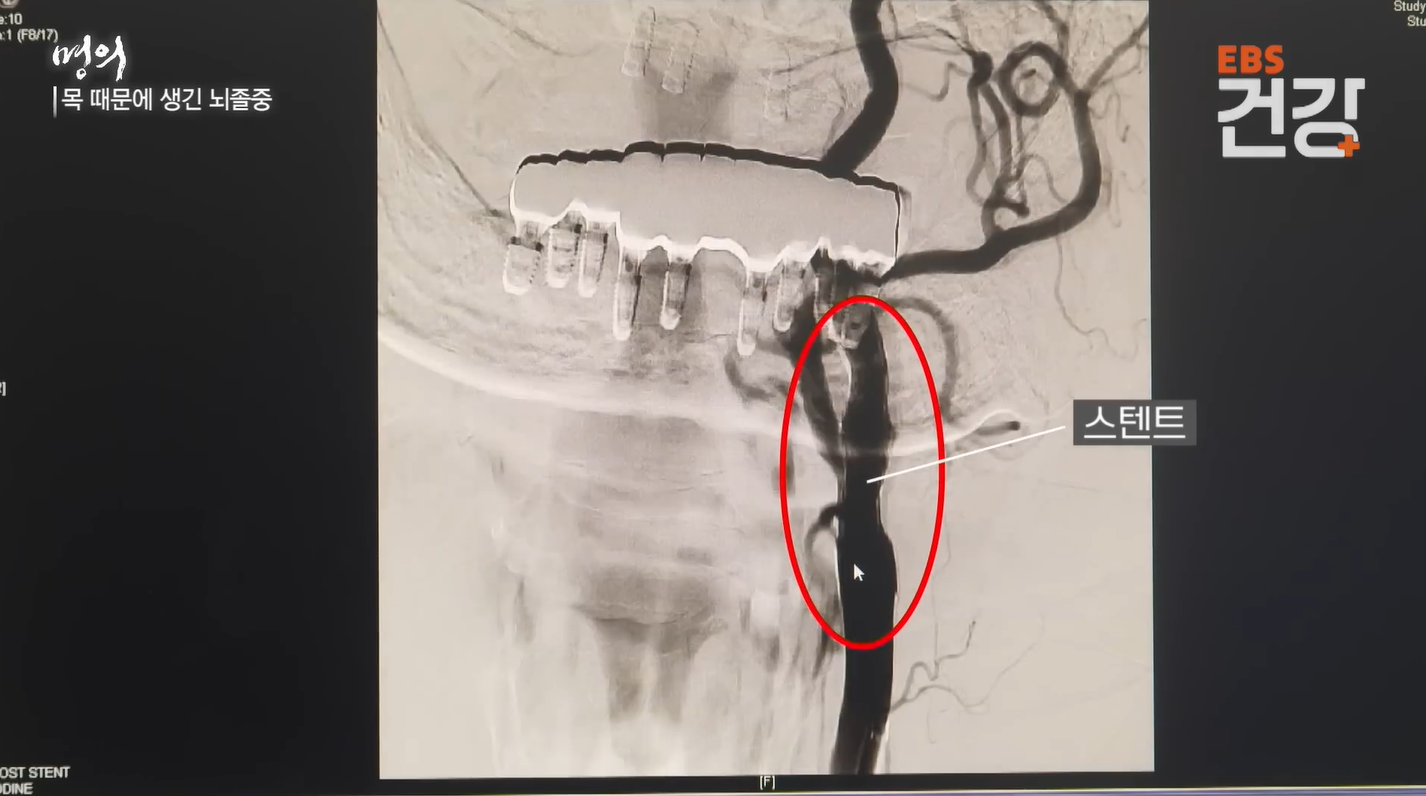

3-2. 경동맥 스텐트 삽입술 (시술)

- 그물망 삽입: 사타구니를 통해 가느다란 관을 넣어 좁아진 부위에 금속 그물망(스텐트)을 펼쳐 혈관을 넓힙니다.

- 안전장치: 시술 중 혈전이 뇌로 날아가지 않도록 색전 방지용 필터를 미리 설치하는 것이 핵심입니다.